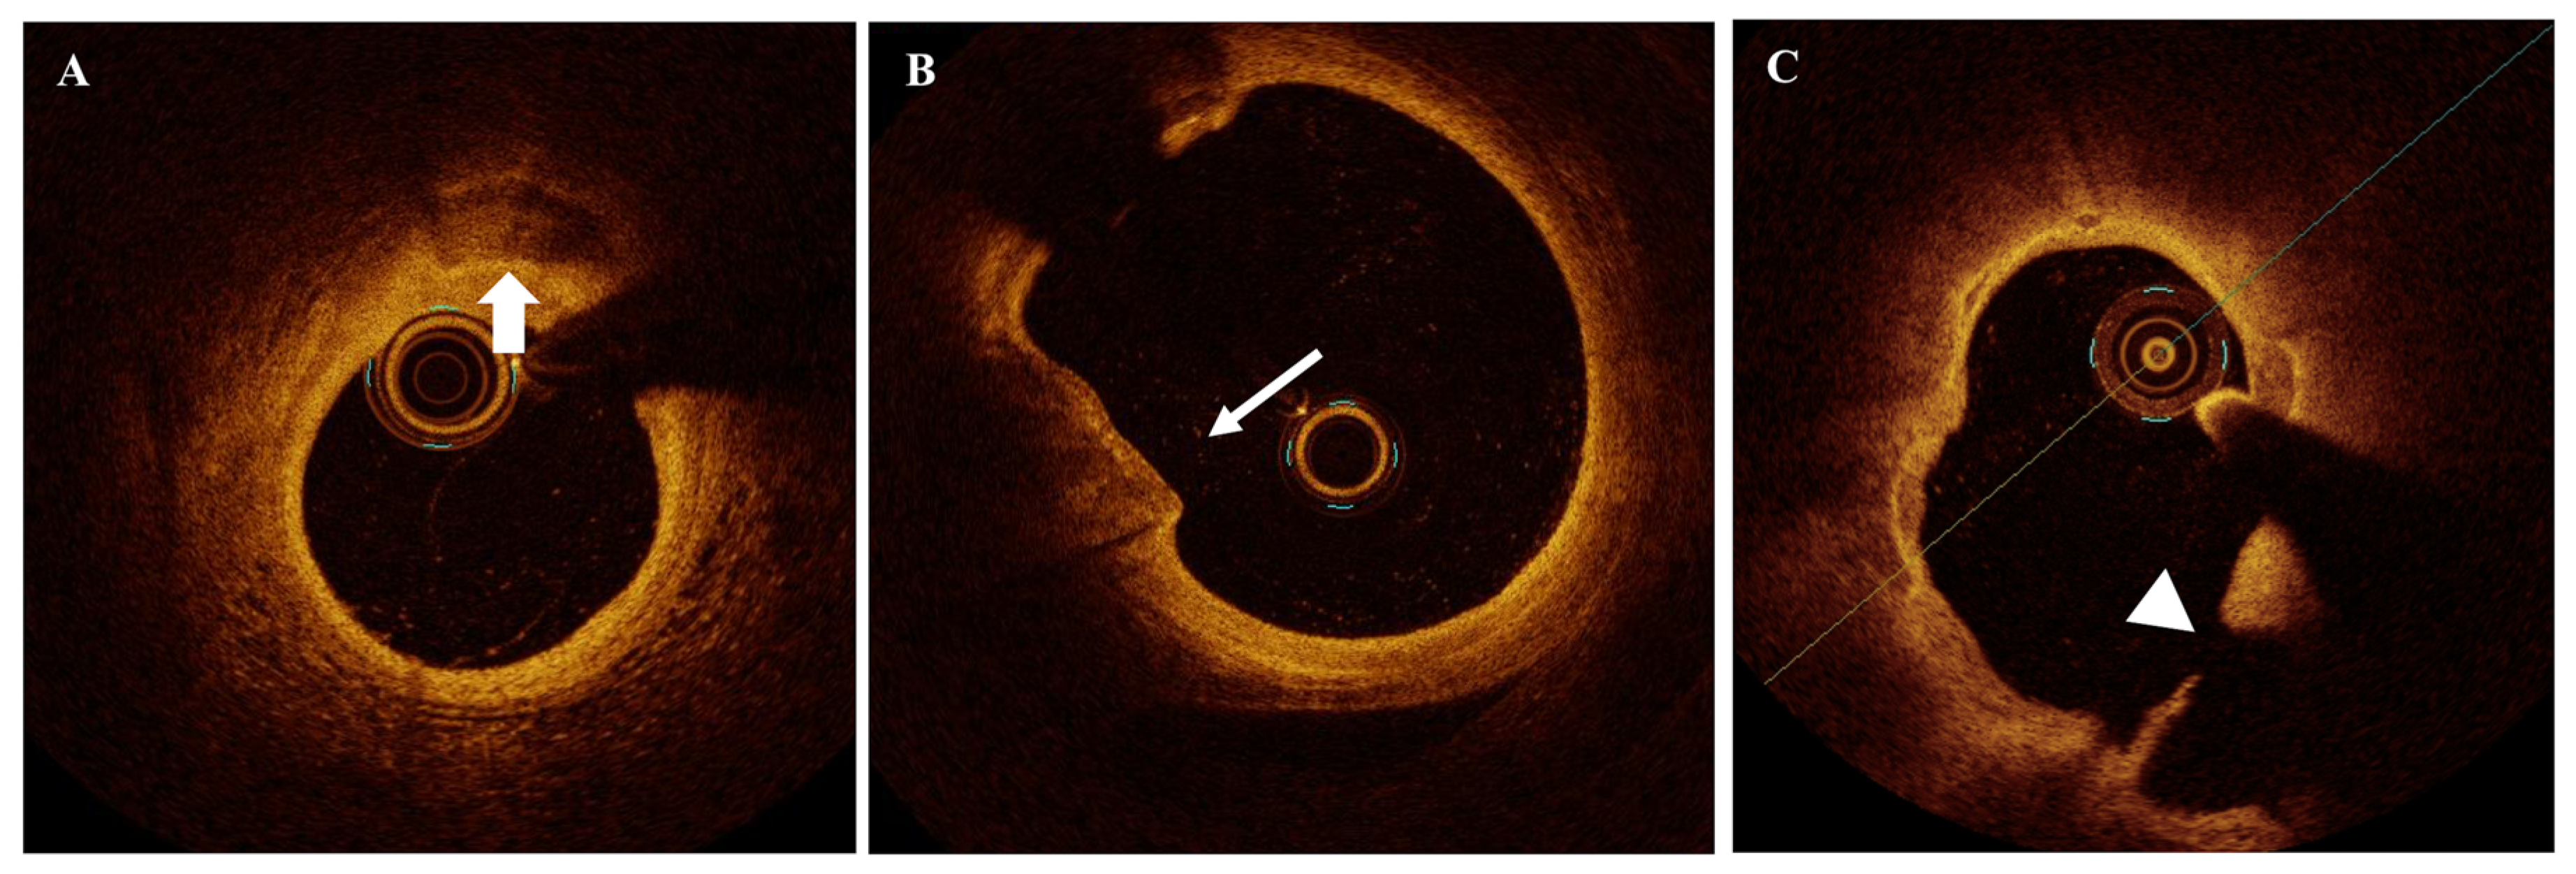

2.8. Previous Ruptures (Cavities Within the Plaque in Stable Patients)

2.1. TCFA

2.2. Lipid-Rich Plaque and Lipid Burden